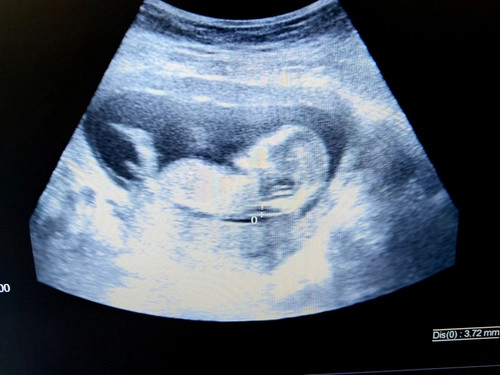

La clarté nucale est un espace rempli de liquide situé à l’arrière du cou du fœtus. C’est une zone naturellement présente chez tous les bébés au début de leur développement. Lors de l’échographie du premier trimestre, entre 11 et 13 semaines d’aménorrhée, ce pli est mesuré précisément.

L’objectif ? Vérifier que son épaisseur est dans les normes attendues. Car une clarté nucale trop épaisse peut être un marqueur de certaines anomalies chromosomiques, comme la trisomie 21, ou de malformations cardiaques.

Mesurer l’espace derrière sa nuque, en millimètres

En général, une clarté nucale est considérée comme “normale” lorsqu’elle est inférieure à 3,5 mm. Au-delà, cela peut augmenter le risque de certaines anomalies, mais cela ne signifie pas automatiquement qu’il y a un problème.